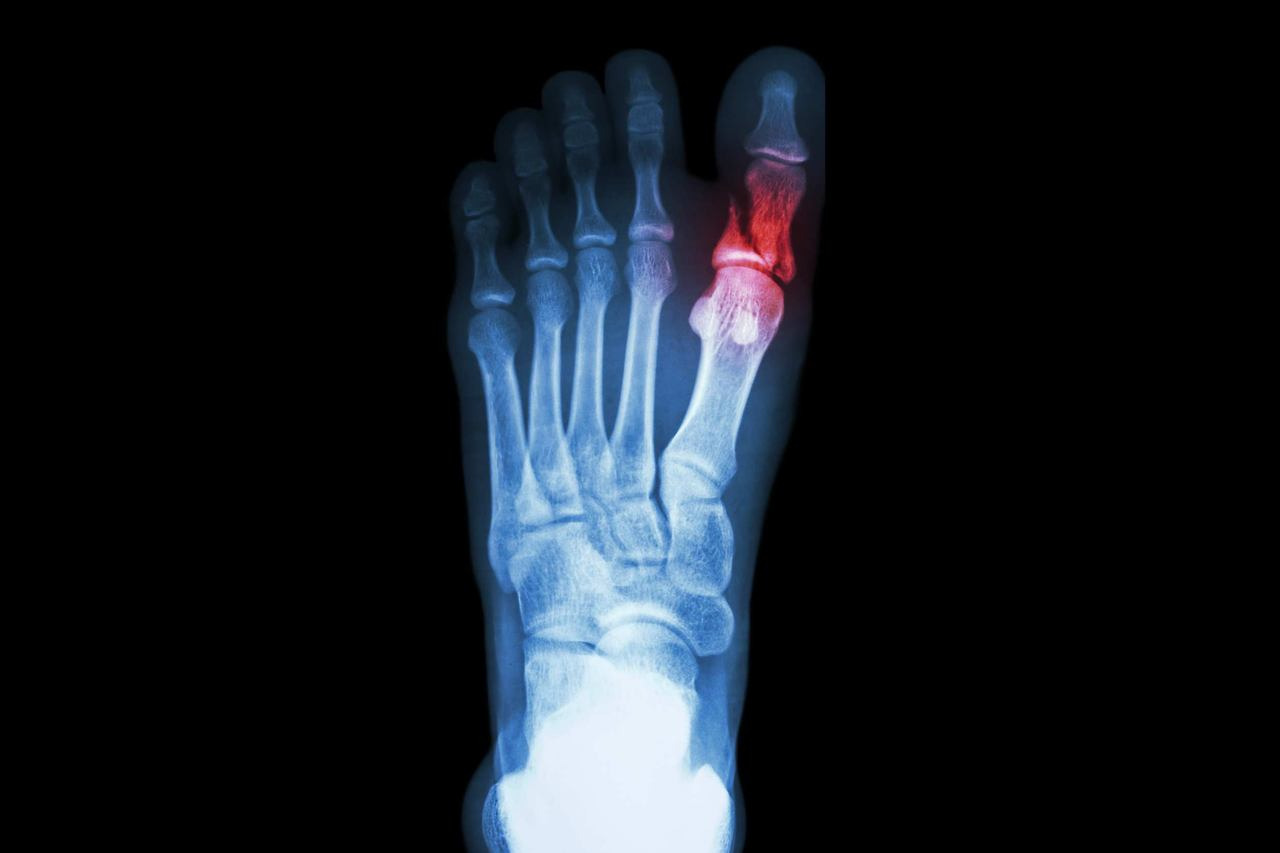

발가락 골절은 손상 형태에 따라 몇 가지로 구분된다. 의료기관에서는 이를 영상검사로 확인한 뒤, 골절 유형에 따라 치료 및 위로금 지급액을 다르게 산정한다.

피부가 찢어지지 않고 뼈 안쪽에서만 골절이 일어난 경우로, 새끼발가락 골절 대부분이 여기에 속한다. 외부 출혈은 없지만 통증과 부종이 심하며, X-ray로 확인해야 진단이 가능하다. - 개방성골절

병원에서는 우선 X-ray 촬영을 통해 뼈의 어긋남 여부를 확인한다. 단순 골절이라면 부목 고정이나 깁스로 충분하지만, 뼈가 틀어졌거나 조각난 경우에는 정복술 또는 핀 고정 수술이 필요하다. 치료 과정은 다음과 같이 진행된다.

- 진단: X-ray 또는 CT 촬영으로 골절 위치와 형태를 파악